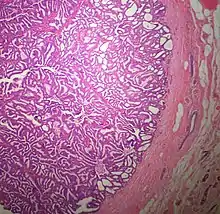

The microscopic histopathology of typical PDCIS lesions (refer to adjacent high-power photomicrograph) prepared with a hematoxylin and eosin stain consists of mammary ducts that have papillary fronds (i.e. thin, finger-like or leaf-like structures) lined with one or several layers of neoplastic, columnar-shaped epithelial cells (i.e. tall, narrow cells with their nuclei close to the site of their ductal attachment).[4] The fronds have branching fibrovascular cores. Epithelial cells lining the fronds' inner surfaces commonly form solid, cribriform (i.e. large nests of cells perforated by many rounded, variably sized spaces), or micro-papillary patterns. There may be a second population of epithelial cells lining the papillae that have abundant clear cytoplasm in addition to the usual neoplastic epithelial cells which line the papillae. These cells, which are not myoepithelial cells, have been termed globoid cells.[7] They have eosinophilic cytoplasm (i.e. pink or red cytoplasm due to its uptake of eosin stain).[6] PDCIS tumors with these cells have been termed dimorphic variants of PDCIS.[3] Myoepithelial cells are typically present at the periphery of the fronds but absent within the involved ducts.[4][7] The presence of a fibrous capsule and/or absence of peripherally located myoepithelial cells are strong indicators that the tumor is an ESP rather than a PDCIS.[3] PDCIS tissues may also contain areas of "Comedo-type necrosis", i.e. areas where dead cells have accumulated.[6]